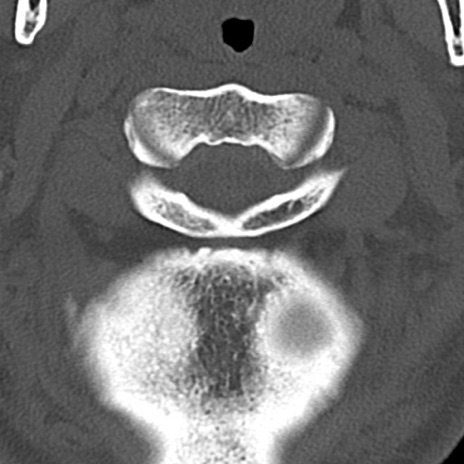

頚椎CT

横断像